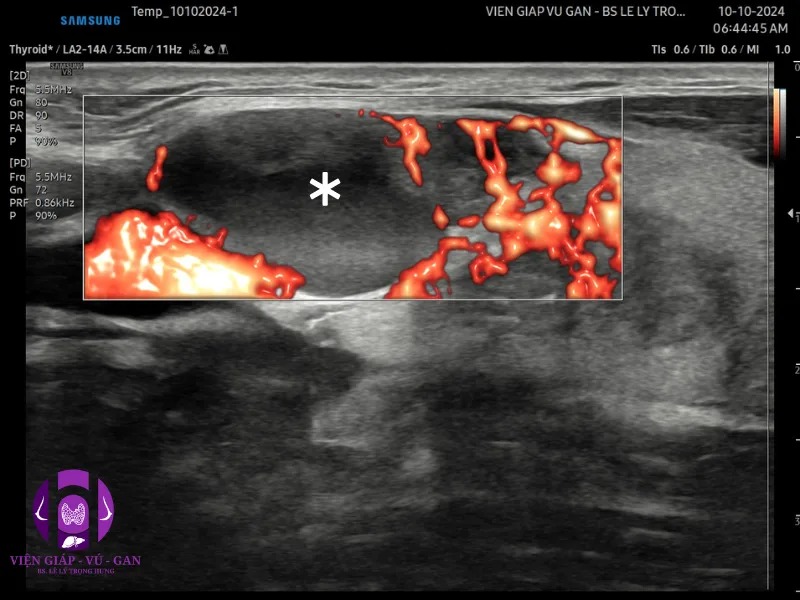

SIÊU ÂM ( Sumsung V8 ) ghi nhận :

- Tuyến giáp thùy phải: nửa trên có nhân đặc echo kém, bờ không đều, vi vôi, mạch máu phân bố ngoại vi và rải rác trung tâm kt#22x10x18mm

- Hạch cổ phải nhóm III có 1 hạch echo kém, mất rốn, hóa nang , kt #24x20mm